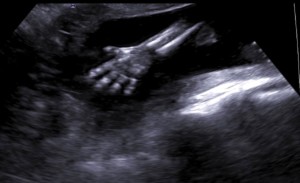

در این تصویر می توانید دست باز جنین را در هنگام بررسی جنین در هفته 20 ببینید. می توانید کف دست و تمام پنج انگشت را مشاهده کنید.